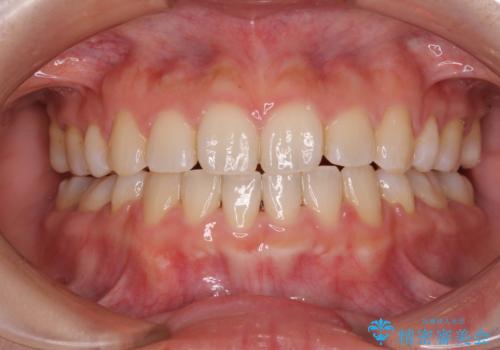

口が閉じられない ワイヤー装置による矯正治療

上下ともに顎が小さく、歯列が前方に突き出していたため、上下左右の第一小臼歯4本を抜歯し、口元の突出感を改善していくこととしました。

口元の突出感が改善されると睡眠中の口呼吸が予防でき、鼻炎などの疾患予防に繋がると言われています。